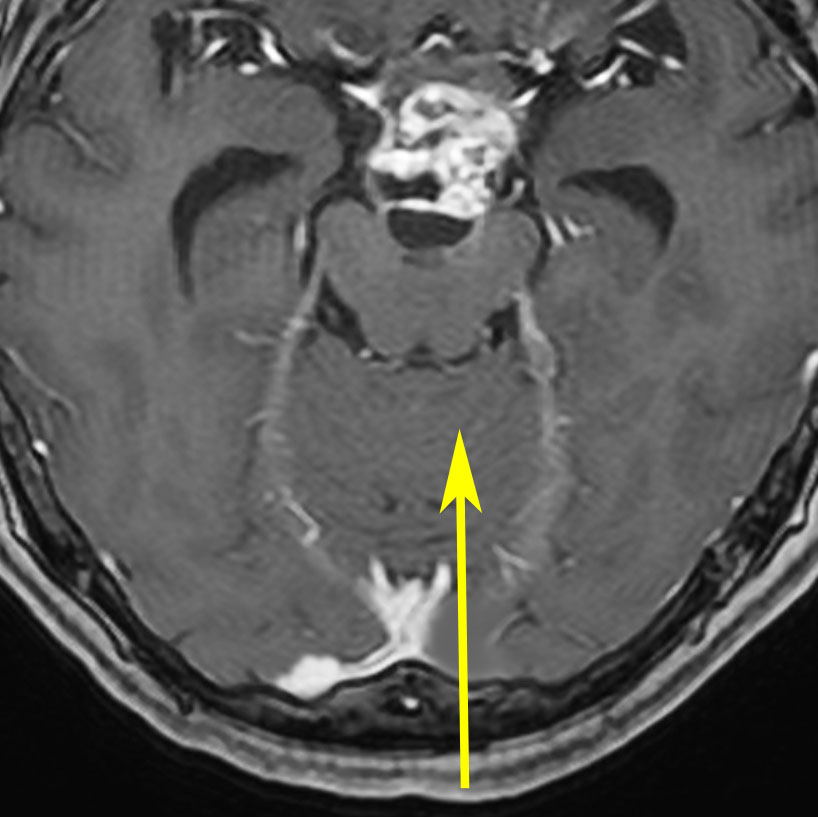

小さな松果体奇形腫です。

OTAでこの奇形腫を見ようとする場合に,テントを静脈洞交会の低い位置まで切断しなければ,直静脈洞の横から松果体部をみることはできません。また,黄色の矢印の方向に視野が入るので,まず最初に邪魔になるのは小脳上極です。上小脳層を左右ともに十分剥離すると,小脳が可動化して,その向こうに,precentral cerebellar veinが見えます。このveinをガレン大静脈への流入部から小脳前面に沿って剥離していくと,小脳上極がさらに可動化して松果体への視野が開ます。